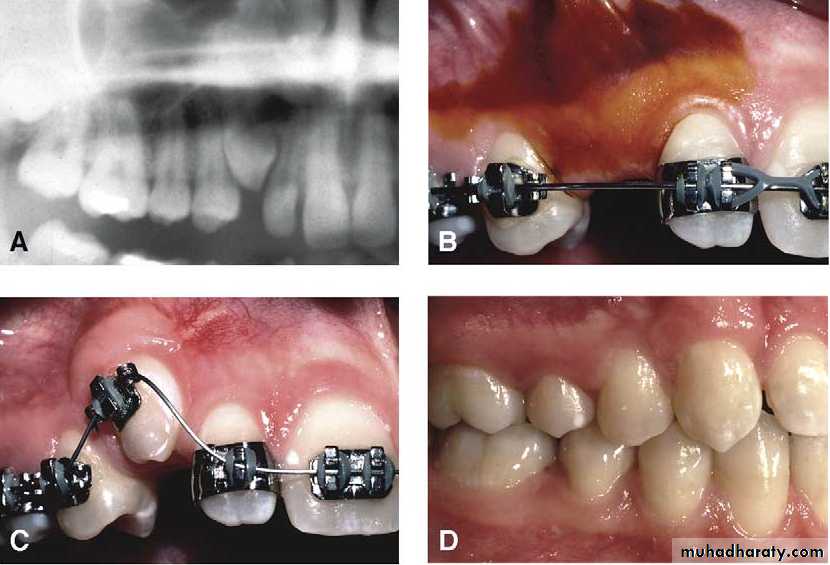

Radiological examination

The periapical radiograph provide a detailed picture of the tooth and its surroundings and is helpful for demonstrating the degree of root formation of the canine , apical curvature , the existence of any root resorption affecting the adjacent lateral incisor and the presence of an associated cyst .Mosul university- College of dentistry-oral & maxillofacial surgery department

The relative radiopacity of the crown of the impacted canine may assist in the determination of the tooth position (the more radiopaque lie palataly )

The occlusal views are 3 types ,anterior , vertex , and true . the vertex occlusal technique is the only technique used for determination of the true position of the impacted tooth.

Surgical exposure :the path of eruption is not obstructed

Surgical exposure with orthodontic treatment : the path of eruption is obstructed

Surgical exposure with orthodontic treatment (palatal approach )